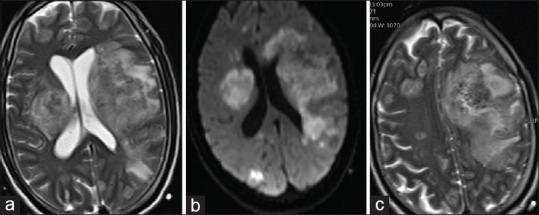

登革热脑炎——一组罕见病例

Dengue encephalitis - An unusual case series.

Dengue infection can take on many different forms, ranging from no symptoms to a mild fever, all the way to a severe condition known as dengue shock syndrome. Although the typical symptoms of dengue are well known, the virus can also cause rare neurological complications. Dengue encephalitis is a severe form of neuroinvasive dengue that can be fatal as the virus directly affects the central nervous system. This case series provides a comprehensive overview of dengue, its clinical spectrum, and the potential for severe neurological complications such as dengue encephalitis. It highlights the importance of considering dengue as a possible diagnosis in patients with encephalitis, particularly during a dengue epidemic.

摘要

登革热感染可呈现多种不同形式,从无症状到轻度发热,直至发展为一种名为登革热休克综合征的严重病症。尽管登革热的典型症状广为人知,但该病毒也可能引发罕见的神经系统并发症。登革热脑炎是神经侵袭性登革热的一种严重形式,由于病毒直接影响中枢神经系统,可能会导致死亡。本病例系列全面概述了登革热、其临床谱以及诸如登革热脑炎等严重神经系统并发症的可能性。它强调了在脑炎患者中,尤其是在登革热流行期间,将登革热视为一种可能诊断的重要性。